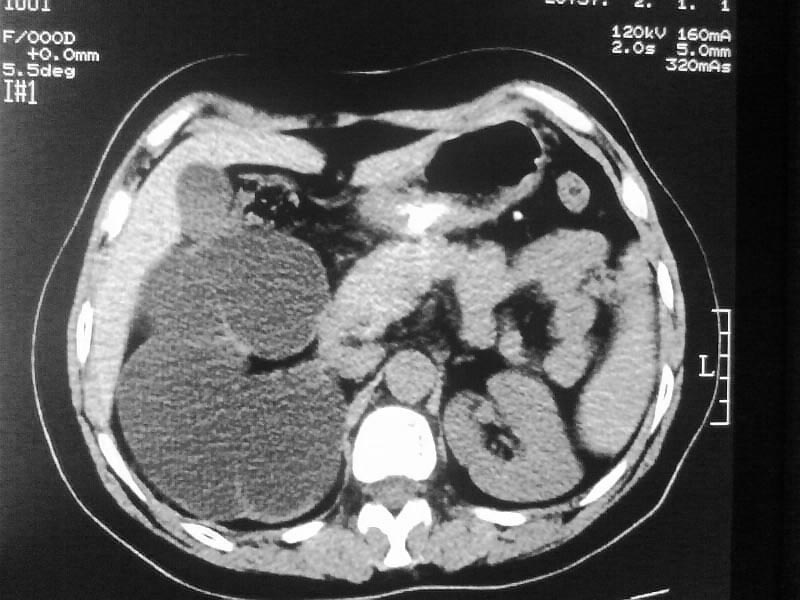

标题: CT20044:女,45岁,腰痛2年,双肾结石,右输尿管结石,右肾重度积 [打印本页]

标题: CT20044:女,45岁,腰痛2年,双肾结石,右输尿管结石,右肾重度积

加扫下输尿管和膀胱吧,先排除下面的大结石所致的积水;

不像普通的积水,密度像是积脓;

多囊肾可以排除。

支持双肾结石、右输尿管上端结石,右肾重度积水

双肾结石、双输尿管结石并右肾积水。